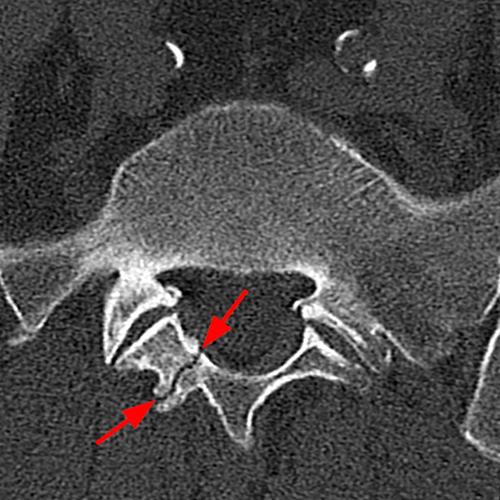

Case 2: 19-year-old male baseball player with acute onset of back pain after hitting a ball. Axial T1-weighted (2A) and T2-weighted (2B) images are provided. What are the findings? What is your diagnosis?

Case 2: T1-weighted (4A) and T2-weighted (4B) axial images show T1 hypointensity and T2 hyperintensity (arrowheads) in the left lamina of L5 adjacent to a small hypointense line (arrows) which traverses the lamina.

Case 2: Acute left-sided laminolysis